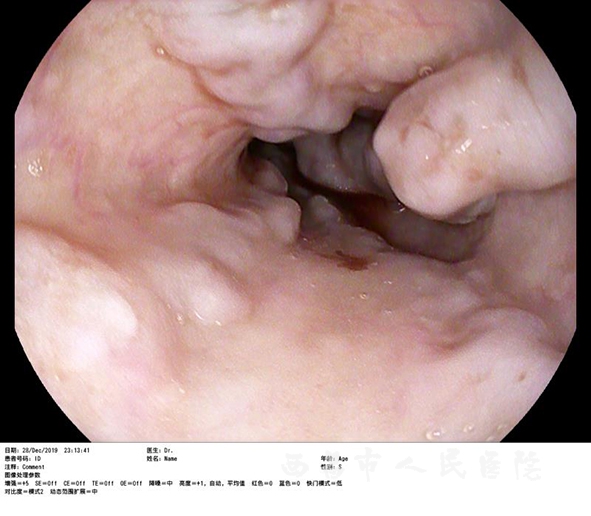

抢救过程中,芶雪琴主任通过内镜检查发现患者食管下段4-5条蓝色静脉曲张,呈蚯蚓状,瘤样,直径约0.5-0.6cm,胃内见大量鲜红色血液及食物残渣潴留,视野极不清楚,在不断的清洗胃内积血,食物残渣后,渐渐显出贲门口处环绕镜身的多条粗大的静脉曲张,通过专业谨慎的评估,出血就在于此,芶雪琴主任立即对胃底曲张静脉进行硬化剂、组织胶注射止血术。耗时2个多小时,在28日凌晨1点多芶主任医护团队完成了手术的最后一个步骤,成功把病人从死神手中夺了回来。看着患者转危为安,各项生命体征逐步恢复到安全值已是凌晨3点,参与抢救的全体医护人员均如释重负,将抢救成功的激动心情分享给焦急等待的病患家属。

见食管胃底静脉曲张破裂出血

打组织胶、硬化剂后血管硬化实变,胃底静脉曲张明显好转,出血停止。